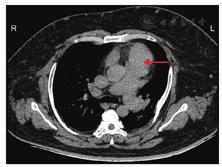

患者男,38岁。因"外伤至阴囊、双下肢肿胀并疼痛3 d余"就诊我院急诊科,急诊科给予对症治疗后好转。因患者为重度肥胖症,我科参与会诊后,收治拟行减重手术治疗。患者入院体格检查:体质量155 kg,身高169 cm,BMI 54.27 kg/m2,腹部膨隆,呈蛙状腹,腹软,全腹无压痛反跳痛,墨菲征阴性,肝、脾、肾区无叩击痛,未闻及肠鸣音。双下肢轻度凹陷性水肿。阴囊水肿。全身可见多处皮肤褶皱处色素沉着、角化过度。血常规及实验室指标检查:RBC 8.31×1012/L、Hb 195 g/L、尿酸670 μmol/L、Alb 29.9 g/L、D-二聚体1.26 mg/L。激素指标检查:睾酮97.31 pg/mL、雌二醇54.07 pg/mL。营养指标检查:血清转铁蛋白3.83 g/L、血清前白蛋白0.091 g/L、糖化血红蛋白7.10%、脑钠肽961 pg/mL。血气分析检查: pH 7.21、二氧化碳分压(PaCO2)95.5 mmHg(1 mmHg=0.133 kPa)、氧分压(PaO2)31.8 mmHg、血氧饱和度45.8%、实际碳酸氢根42.7 mmol/L、碱剩余值10.0。口服糖耐量试验血糖值:0.5 h为5.64 mmol/L、1 h为8.14 mmol/L、2 h为8.92 mmol/L、3 h为6.29 mmol/L。血清C肽1.33 ng/mL。胸部CT检查:(1)双侧肋骨多发陈旧性骨折。(2)双肺上叶、右肺中叶斑片状渗出实变影,考虑感染。(3)心脏增大、肺动脉高压、心包少量积液(图1)。(4)双侧胸膜增厚。(5)腹壁皮肤脂肪层浑浊,双侧腋窝见肿大淋巴结。腹部CT检查:(1)肝左叶低密度灶。(2)脾大。肺动脉造影检查:左肺下叶后基底段分支内充盈缺损。考虑为肺栓塞,肺动脉高压,双肺炎症。心脏超声检查:左右心房、右心室增大,主动脉增宽、室间隔增厚,左心室舒张功能减低。多导睡眠监测(polysomnography,PSG)检查:重度阻塞性睡眠呼吸暂停低通气综合征(obstructive sleep apnea hypopnea syndrome,OSAHS),重度夜间低通气综合征,呼吸紊乱指数(apnea hypopnea index,AHI)81.5次/h、夜间最低血氧饱和度58.0%。